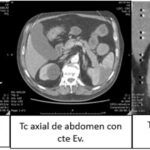

Se trabajó bajo un diseño no experimental, lo que significa que no hubo manipulación de variables, bajo un enfoque horizontal retrospectivo, descriptivo y observacional, donde se empleó la tomografía computada como método diagnóstico principal para el diagnóstico de lesiones quísticas renales. Se utilizó el tomógrafo PHILIPS ACCESS CT (Anexos 13, 14 y 15), emitiendo 16/32 cortes, realizado por médicos especialistas en diagnóstico por imágenes, siguiendo la clasificación Bosniak para categorizar cada uno de los 523 quistes estudiados y poder distinguir por medio del uso de contrastes si correspondían a quistes simples ubicados en la categoría I o a quistes complicados o malignos, los cuales se ubican en las categorías III y IV de Bosniak.

Cabe destacar que para la interpretación de resultados imagenológicos, descripción y posterior reporte de cada tomografía se utilizó el sistema de datos SYNAPSE, realizada por médicos especialistas en diagnóstico por imágenes con más de 20 años de experiencia basándose en la clasificación Bosniak para categorizar cada una de las lesiones quísticas.

Resultados según clasificación Bosniak

- Bosniak I: el 80% de los quistes (418 pacientes) fueron clasificados como Bosniak I, es decir, quistes simples hallados incidentalmente en tomografía computada (TC) y sin necesidad de seguimiento adicional. De estos, 268 pacientes eran de sexo masculino y 150 de sexo femenino (Anexos 17 y 18).

- Bosniak II: el 10% de los quistes (55 pacientes) fueron catalogados como Bosniak II, correspondientes a quistes benignos. Esta categoría incluyó a 36 pacientes de sexo masculino y 19 de sexo femenino (Anexos 19 y 20).